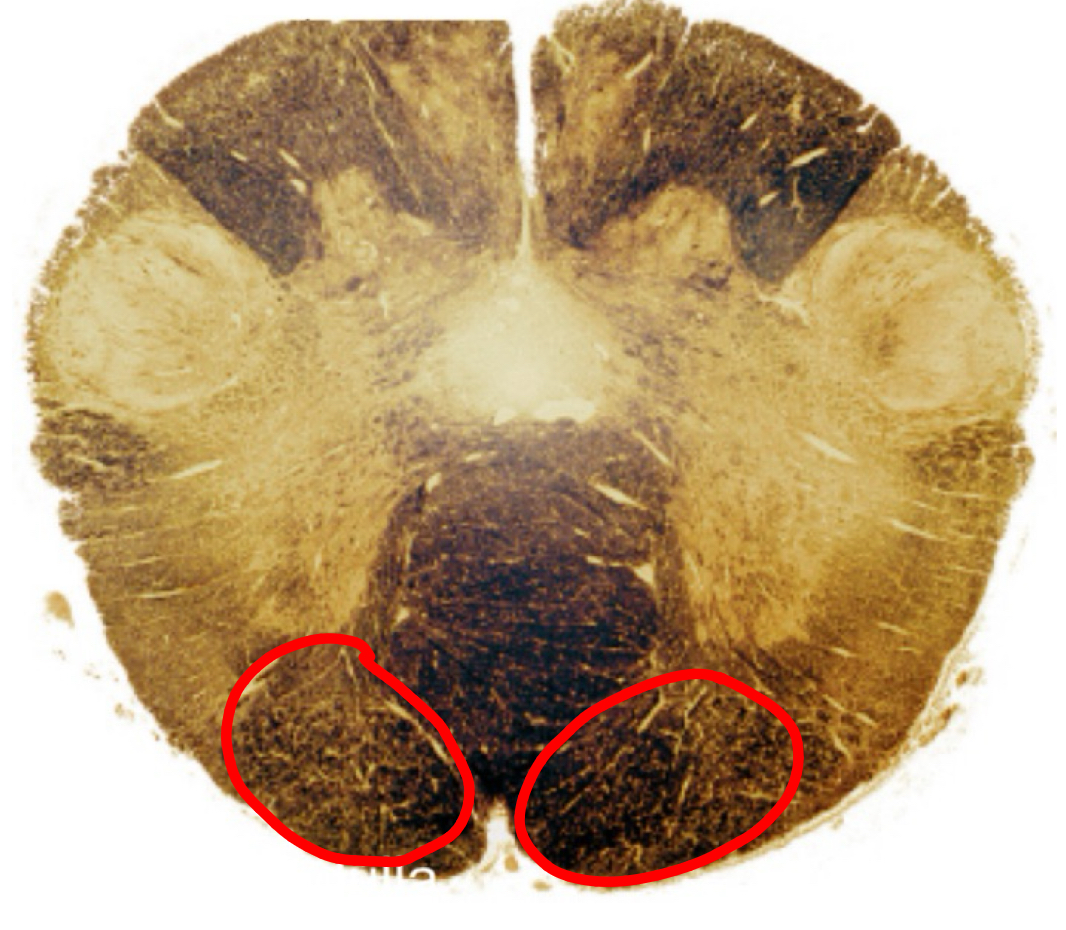

gracile tract caudal medulla II

gracile nucleus caudal medulla II

cuneate tract caudal medulla II

cuneate nucleus caudal medulla II